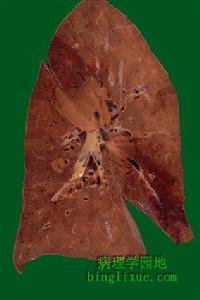

肺嗜酸細胞組織細胞增生症肺纖維化

肺嗜酸細胞組織細胞增生症正常肺顯微鏡顯示肺泡

Travis注意到80%的活檢標本上有血管受累,還常見假脫屑性間質性肺炎(肺實質內在Langerhans細胞間充滿肺泡巨噬細胞)和呼吸性(吸菸者)細支氣管炎(細支氣管腔及周圍氣腔充滿含色素的巨噬細胞);除此之外,發現腔內纖維化常見(80%),以壁性整合、肺泡閉塞和腔內生芽為特點。其中59%為輕度,20%為中度,僅9%為重度。這些所見支持關於腔內纖維化是肺泡塌陷機制、並進展至肺纖維化以及肺重建的假說。間質纖維化小囊腫形成以中、上野占優勢,發生在病變進展期;而且中、上野分布與IPF不同,後者病變多見於下野。病變進一步發展可廣泛累及支氣管血管周圍的肺實質並產生所謂“星狀病變”,為本病的特徵性改變。較陳舊病變細胞成分相對少,產生瀰漫性間質性病理改變,很難與其他終末期肺纖維化區別。囊腫形成的機制尚不清楚,可能是由於陳舊的星狀病變中心壞死所致;也可能是由於進展期支氣管血管病變遠端相對無血管區域的繼發性炎症性病灶而致;最後這些囊腫形成在一定程度上與由星狀病變而導致的近端氣道阻塞有關。LCH病理細胞類型是Langerhans細胞,由單核-巨噬細胞系分化而來。Langerhans細胞正常情況下可見於皮膚、網狀內皮系統、肺臟和胸膜,其胞漿染色淡、核仁大。電子顯微鏡可見典型的五層體胞漿包涵體或Birbeck顆粒(X小體)。雖然這種細胞也可見於健康吸菸者及其他肺病變(如IPF)或正常肺臟,但它的確是LCH的特點,表現為Langerhans細胞成群出現而且數量上明顯超過其他肺病變。但尚未建立起來LCH診斷的定量規範。